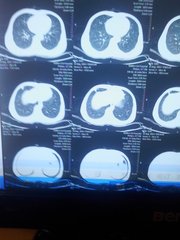

3、胸部影像

合并肺炎时肺内可见片状影像,严重病例片状影像范围广泛。

4、胸部影像

(1)合并肺炎时肺内可见片状影像。

(2)严重病例片状影像范围广泛。